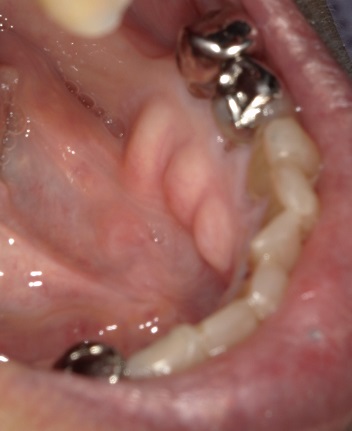

(1)口蓋隆起 torus palatinus

(2)下顎隆起 torus mandibularis